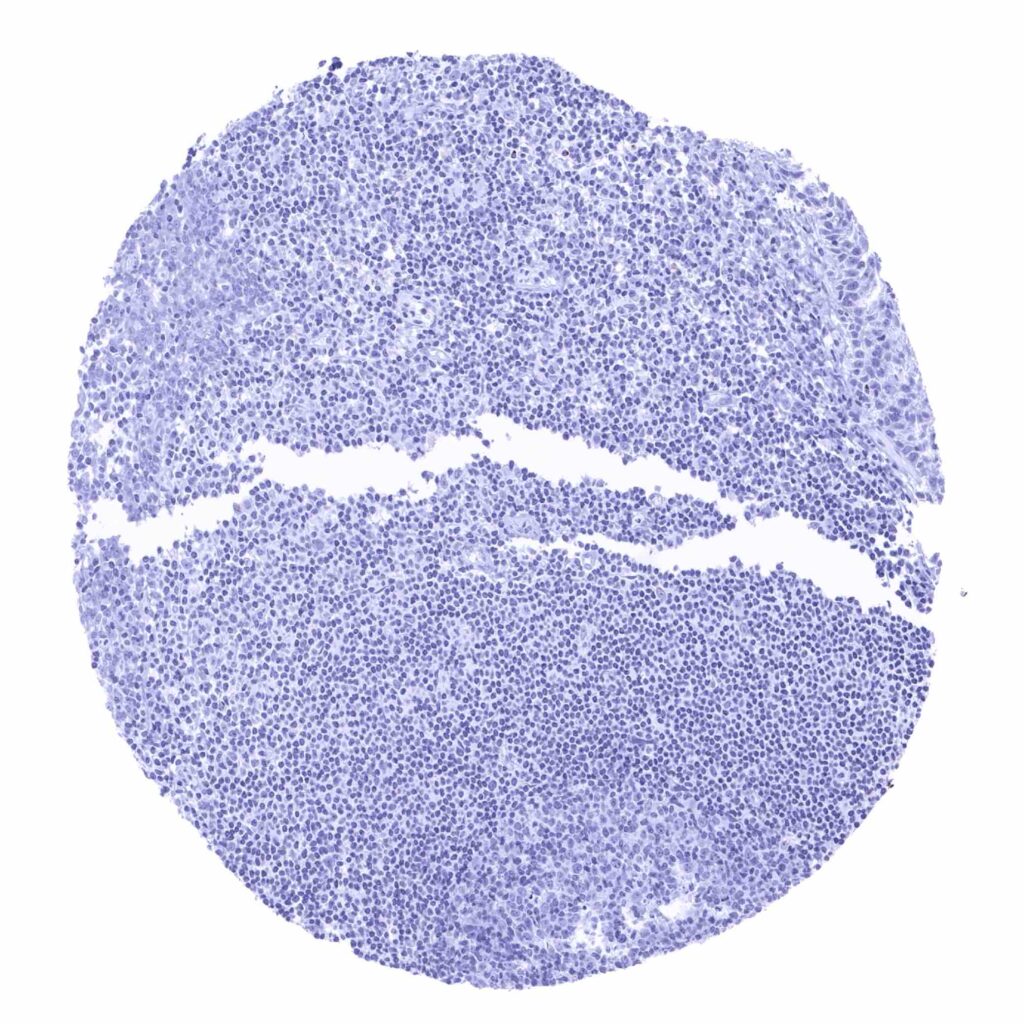

Lymph node

Spleen

Thymus

Tonsil